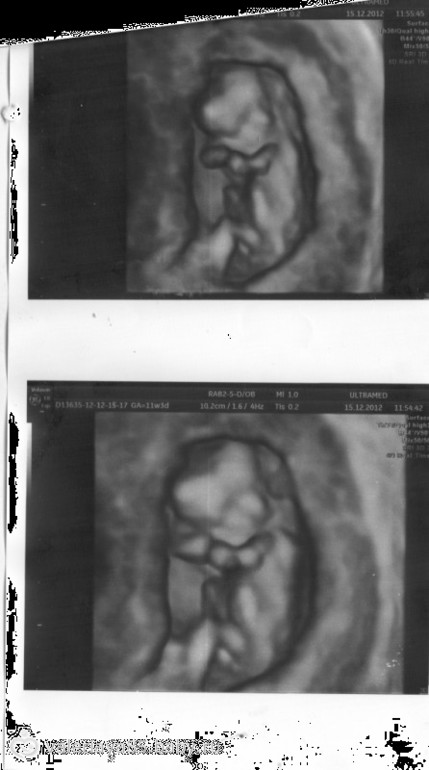

Вот фотка достоинства нашего мальчика в 17 недель ровно

Невозможно ошибиться ))) В 20 недель подтвердили мальчика.